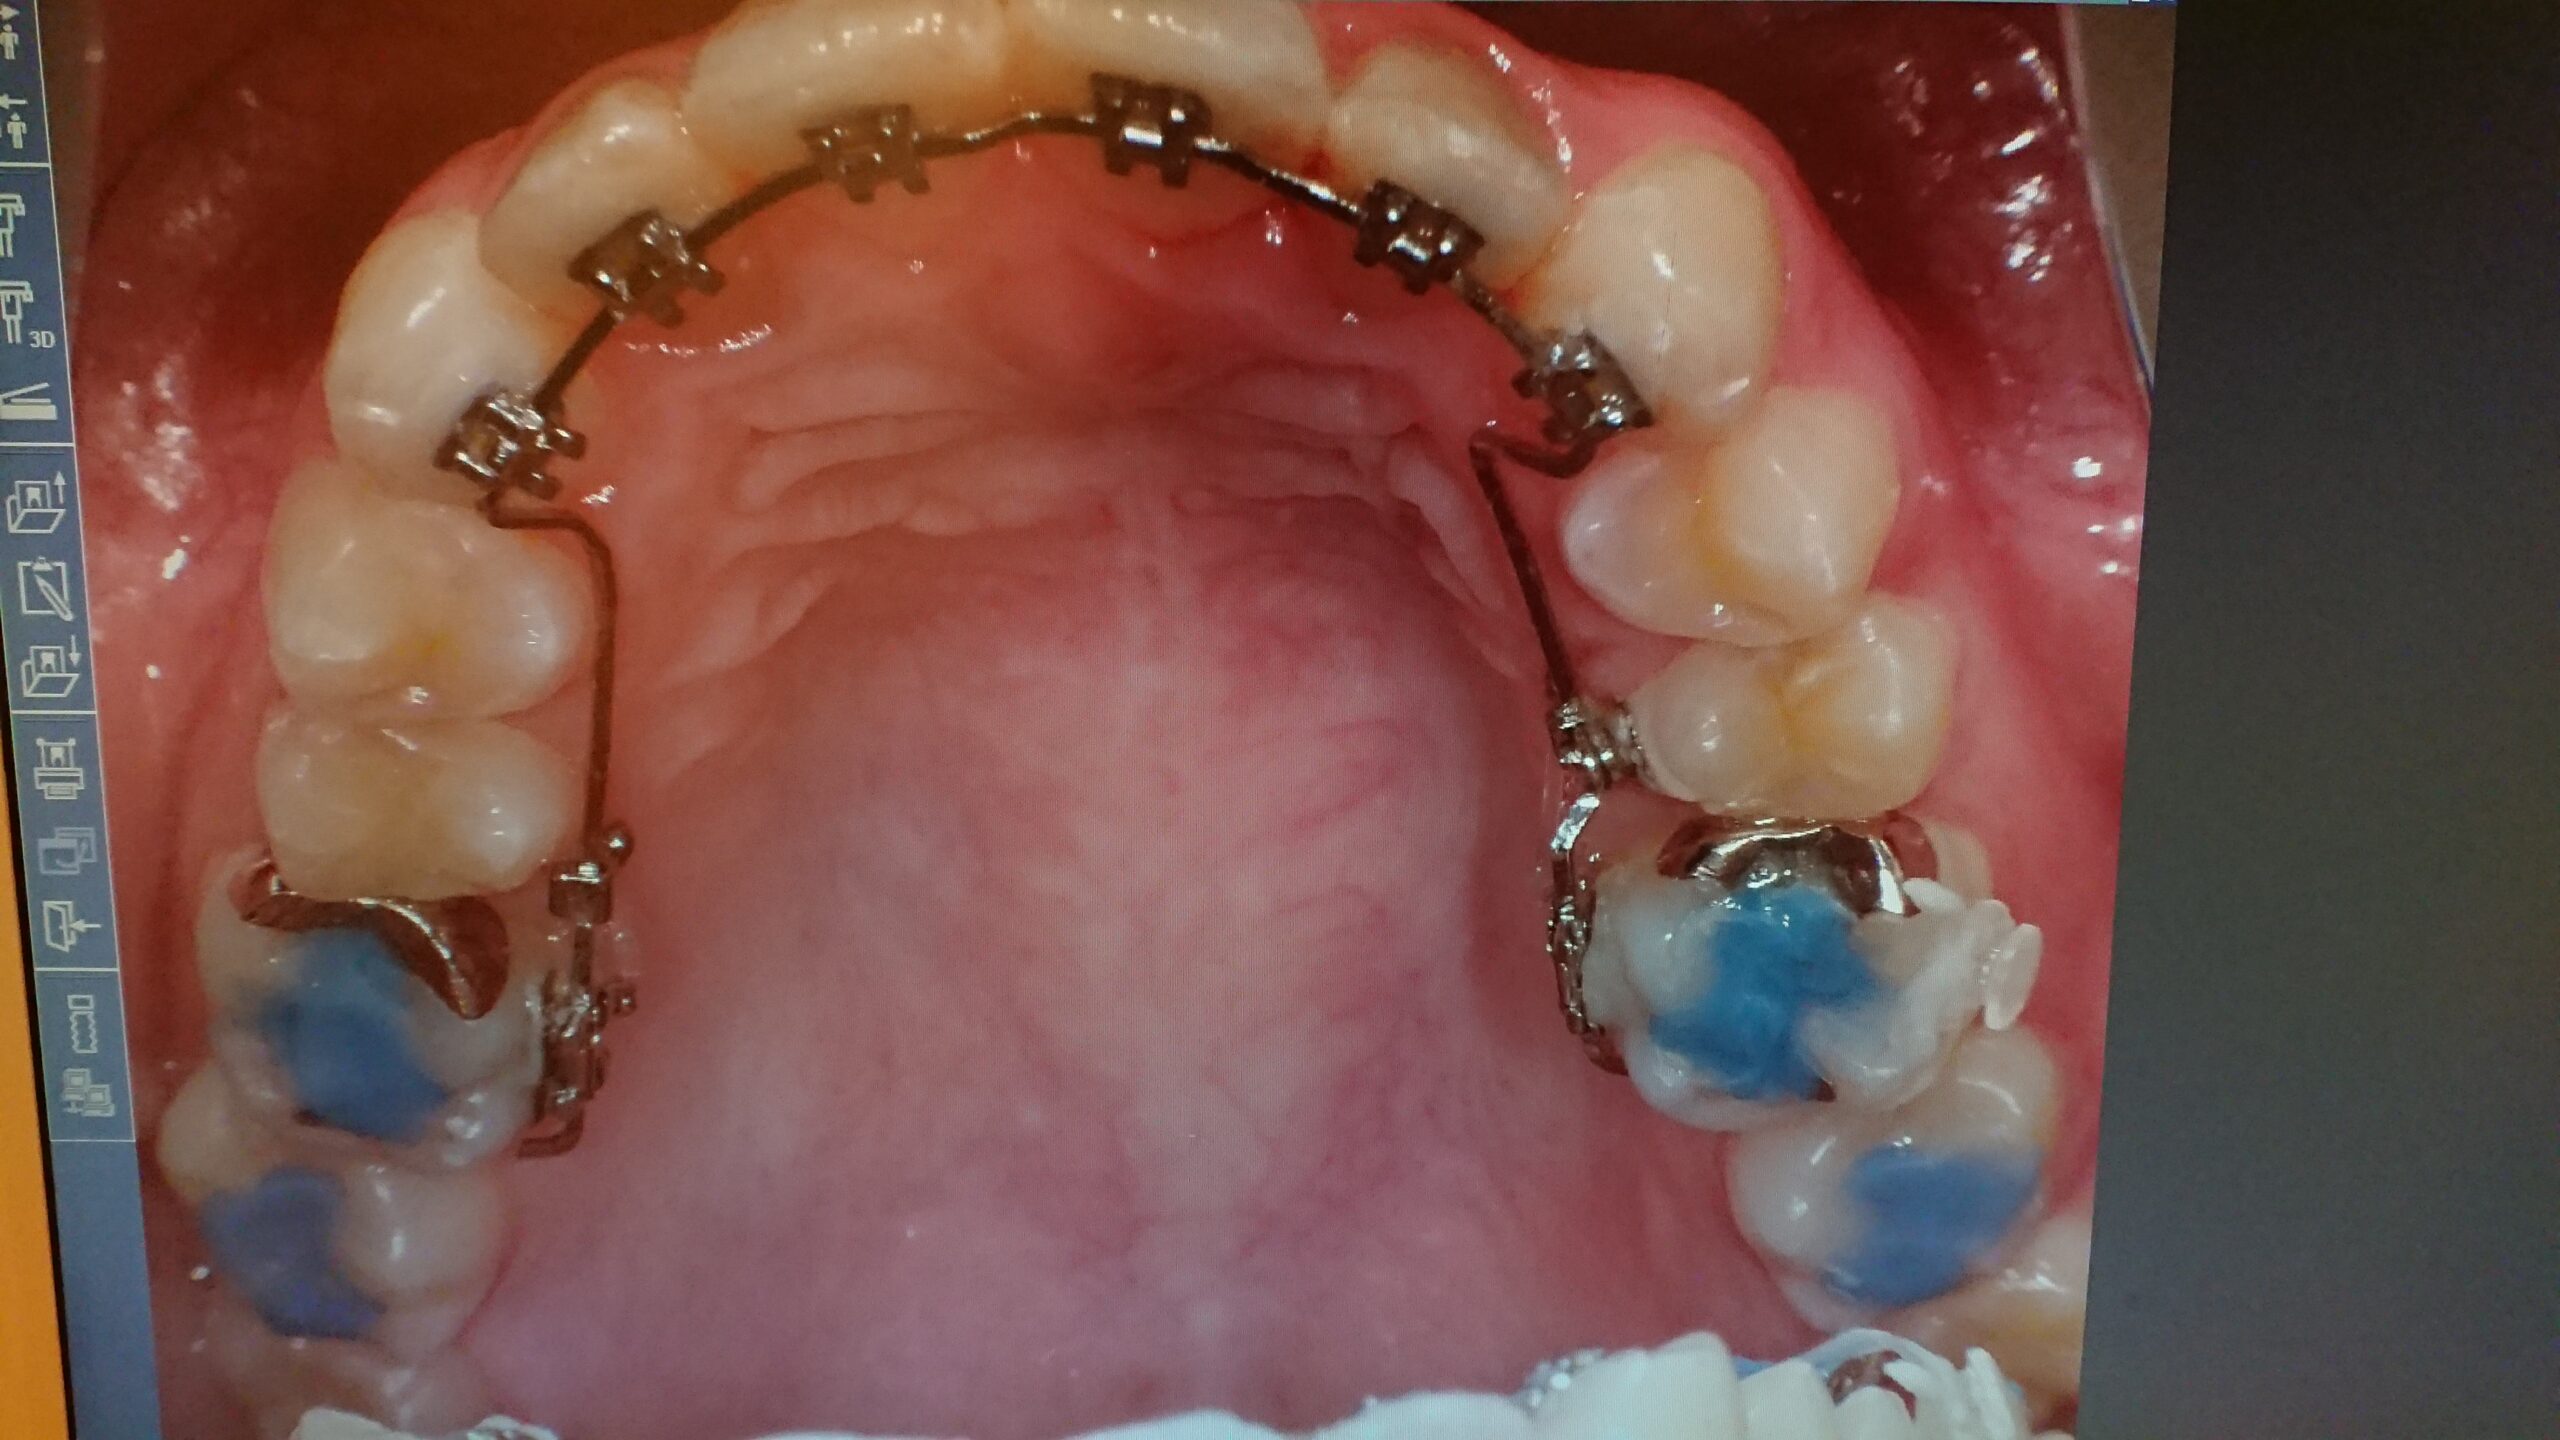

難しい歯の裏側につける矯正リンガル矯正もしてます。最近では元アイドルの方やユチューバーの方たちもリンガル矯正をしてるそうです!気になる方は是非無料相談からお待ちしております(^_^)